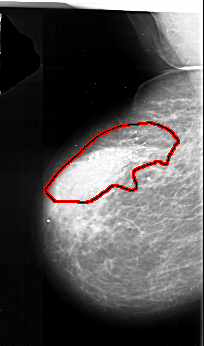

FILE: A_1017_1.LEFT_CC.OVERLAY

TOTAL_ABNORMALITIES 1

ABNORMALITY 1

LESION_TYPE CALCIFICATION TYPE PLEOMORPHIC DISTRIBUTION SEGMENTAL

ASSESSMENT 5

SUBTLETY 5

PATHOLOGY MALIGNANT

TOTAL_OUTLINES 1

BOUNDARY